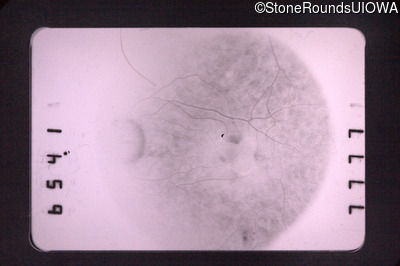

Visit at age: 59 years

Fundus Photography - Right - 20/30

Exemplar